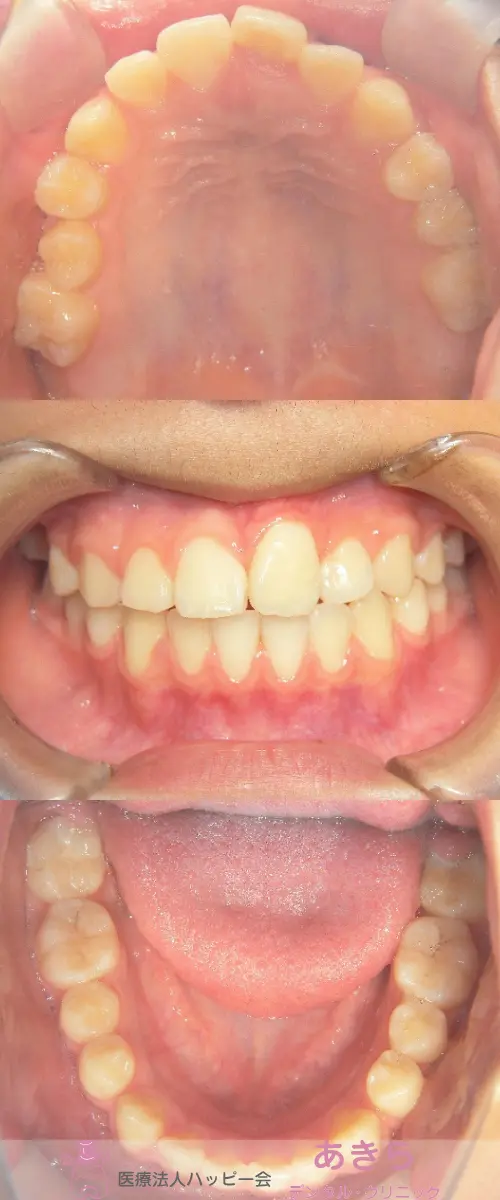

2021年5月8日 口腔内写真(経過時)

2019年4月9日 初診時 ⇒ 2021年5月8日 口腔内写真(経過時)